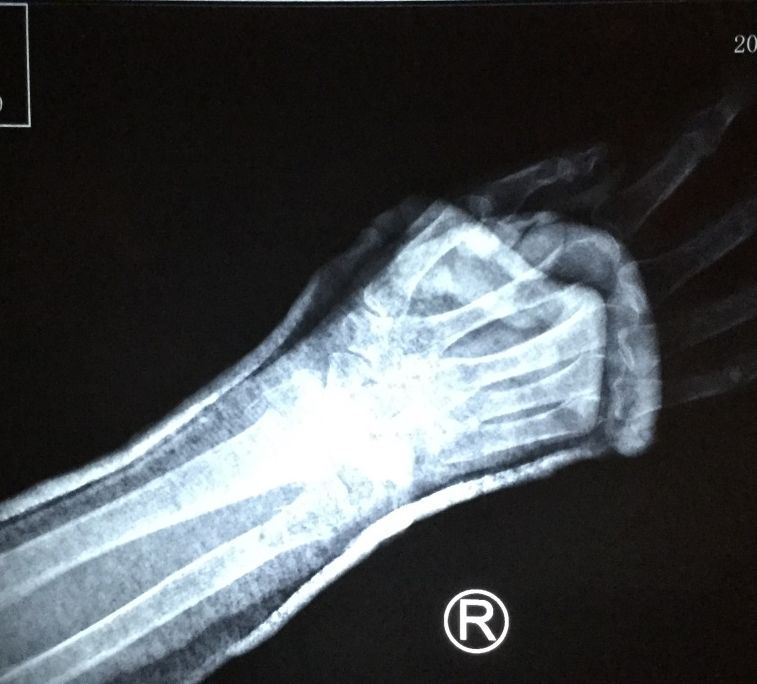

【明慧网二零一九年二月二十四日】〖大陆来稿〗二零一九年一月二十八日上午十时许,现年八十三周岁的北京市民善珍奶奶(化名)在家中客厅穿衣时,不慎摔倒,右手腕部戳在餐桌一角,很疼痛。当时家人将老人送至就近医院检查,拍片结果显示如图1。检查报告单中描述为:右侧桡骨、尺骨远段可见骨质断裂,骨折端掌侧成角,远折端背侧移位(图2)。

'图2'

图2